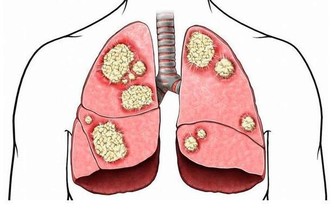

毒素不清,會累積成癌 在大腸癌的發生部位和發生機率中,直腸和乙狀結腸得癌症的機率最高,幾乎有百分之七十的腸癌都集中從肛門上來六十公分的這一段,因為這裡是宿便最容易囤積的地方,毒素都累積在這裡,這段腸子就像家裡的垃圾桶,等到垃圾積滿了才會去倒。咖啡灌腸最主要就是針對這一段腸道進行清腸排毒。

腸癌目前高居國人癌症發生人數的第一名,是有跡可循的,證明現代人飲食中的毒素真的太嚴重,加上排泄不良,宿便的毒素都累積在大腸內。

憋便容易造成三大危害1.當心結腸癌盯上你憋便是不好的生活習慣,大便如果不及時排出,水分就會被腸道反覆吸收,導致大便更加乾結難排。大便中的毒素在體內積累時間過長,有害物質被腸道吸收,就會出現精神委靡不振、頭暈乏力、食慾減退等症狀,嚴重者甚至會引發腸道癌症。